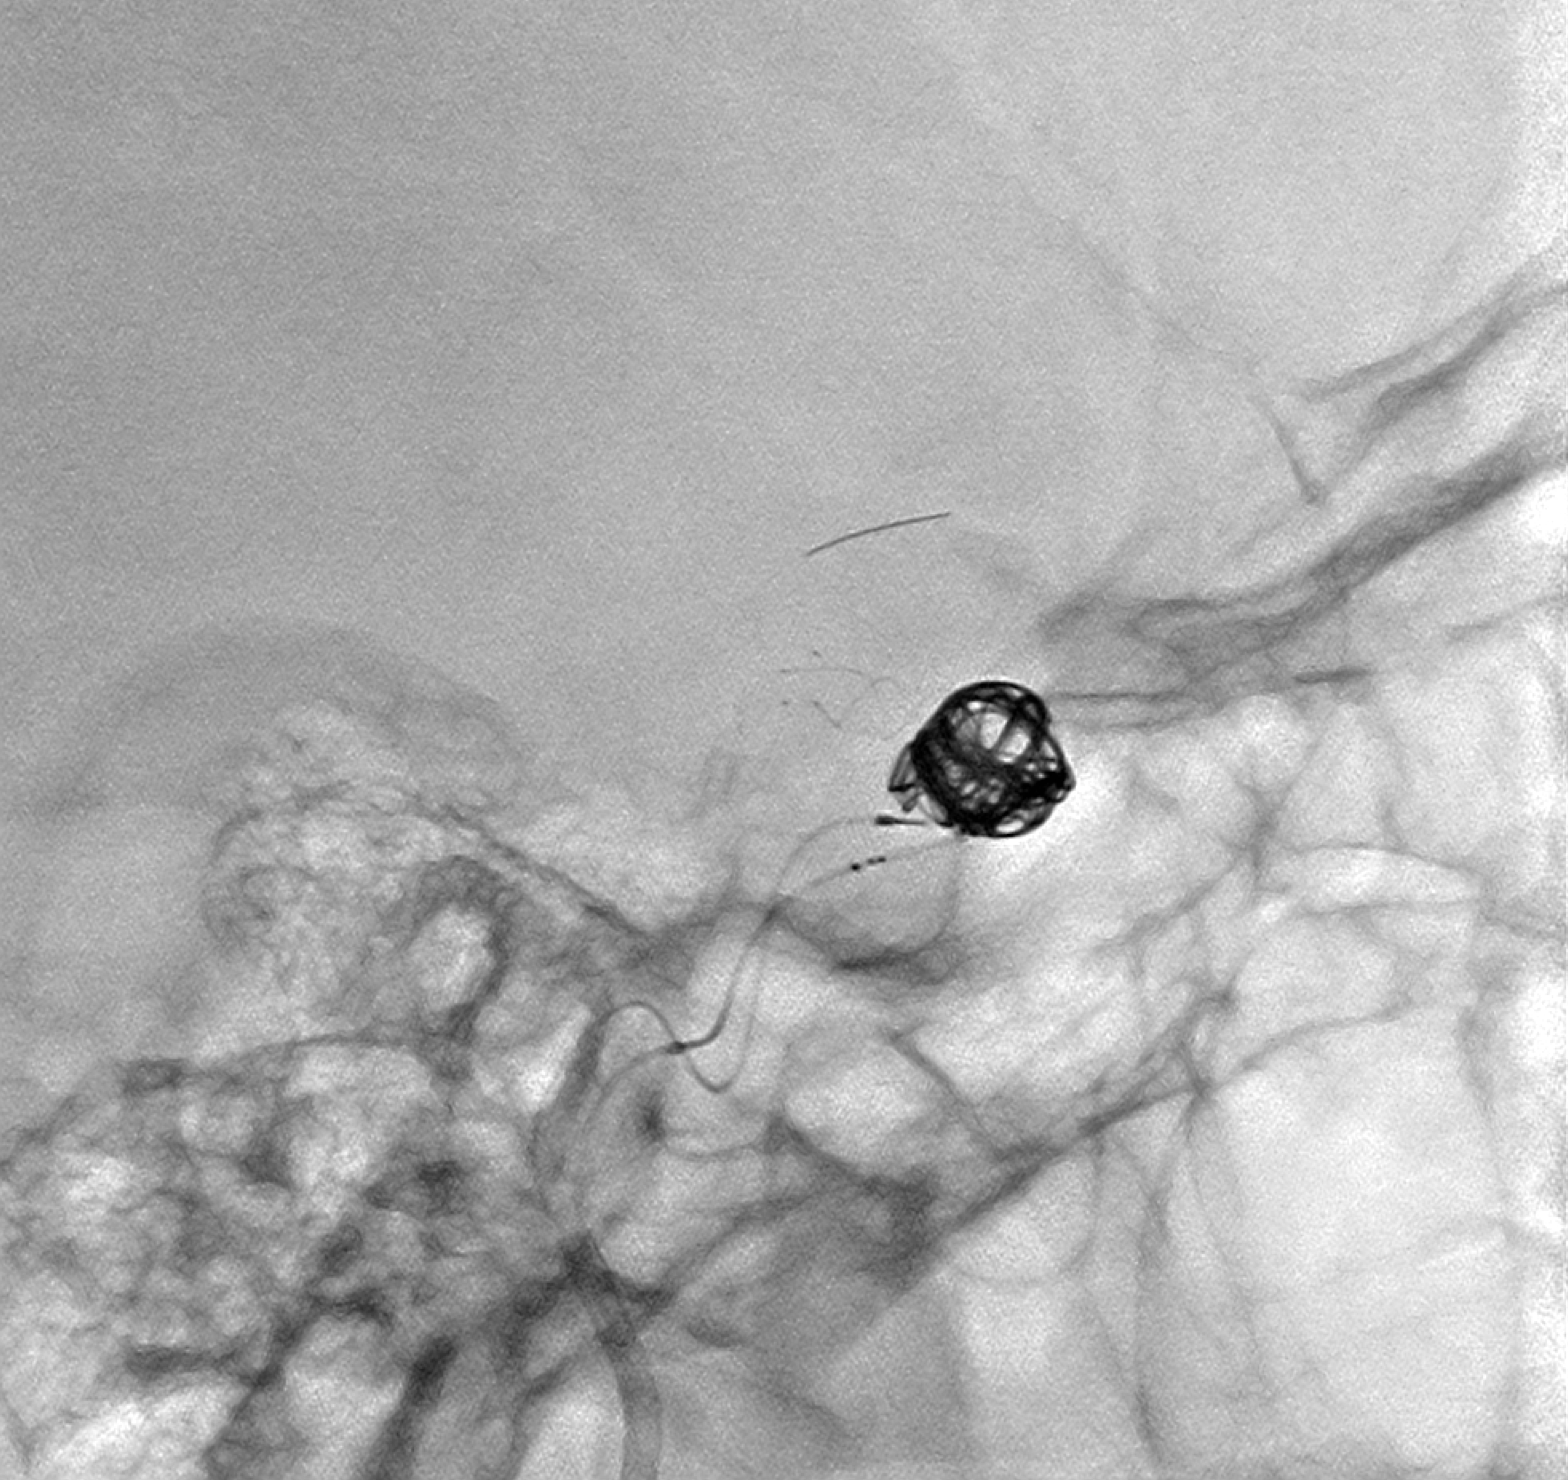

行支架半释放保护瘤颈后,经栓塞微导管逐渐栓塞动脉瘤瘤腔!直至完全栓塞瘤腔!

蒙片显示:支架贴壁良好!部分弹簧圈被支架贴附于近端瘤颈及正常颈内动脉内壁!